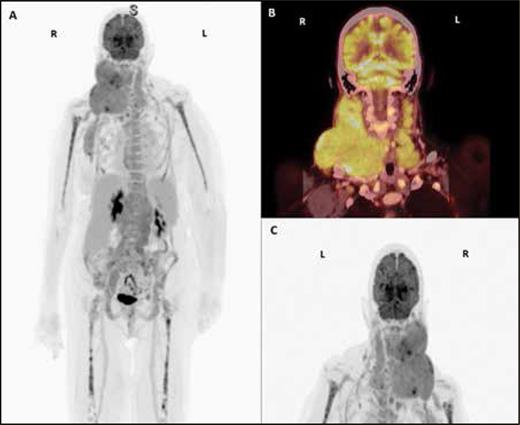

Figure 2

(A-C). PET/CT scan with contrast showing conglomerates of hypermetabolic lymph nodes in the right neck displacing the right oropharynx and extension to the right axilla, with an index lesion of 6.2 x 5.5 cm and standardized uptake value (SUV) of 8.2, and hypermetabolic lymph nodes in the left supraclavicular stations, with an index lesion of 1.7 x 1 cm and an SUV of 3.7.